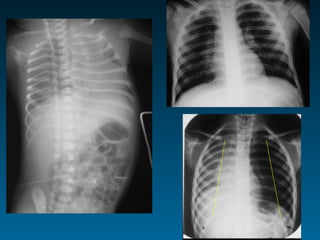

Τεχνικοί παράγοντες: όγκος πνευμόνων

ό   Ποσοστό καρδιάς κάτω από ημιδιάφραγμα στην face α/α

ό   Κυρτότητα-επιπέδωση ημιδιαφραγμάτων

ό   Πρόσθια άκρα των πλευρών και ημιδιάφραγμα

3η-4η: εκπνοή       5η-6η: εισπνοή > 7η:παγίδευση αέρα